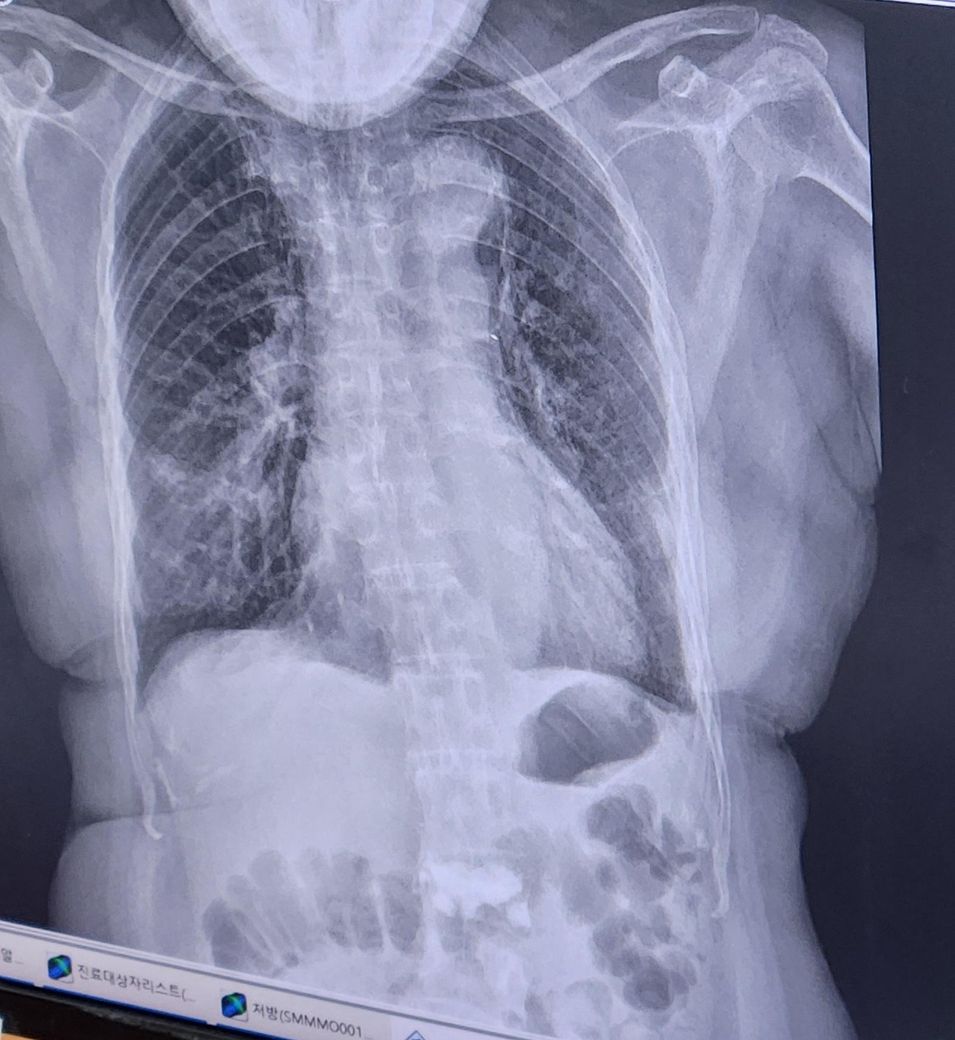

엑스레이 찍고 폐렴판정후

약 5일치먹고 다시가서 엑스레이찍으니

청진소리도 많이좋아지고 엑스레이상에서도

염증이 많이사라졌다하셨습니다.

위에가 판정시 엑스레이